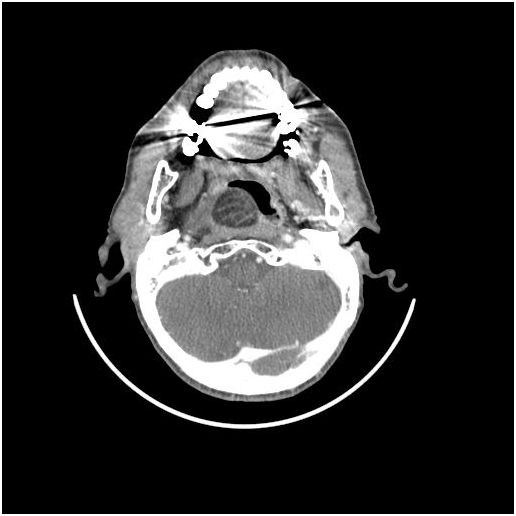

Fibrolipomas have been defined as a subtype of lipomas that are benign soft tissue tumors according to the WHO classification [1]. They differ from classic lipomas with being connective tissue bands involved among the mature adipose tissues [2]. Fibrolipomas have been described in the esophagus, pharynx, colon, trachea and larynx [3,4]. Rarely may they be seen in the oral cavity and in the maxillofacial area. In the oral cavity, fibrolipomas are most commonly found in the buccal region followed by tongue, lower lip and the parotid region; respectively [5,6]. Retropharyngeal space is an area extending from the skull base to the mediastinum, located between the middle and deep layers of the cervical fascia. It contains a small amount of fatty tissue and chains of lymph nodes especially at the suprahyoid level [7]. Lymph nodes and lymphatic channels are the main components of this space [8,9]. Tumors of the retropharyngeal region are extremely rare. The most commonly seen mass is in a form of inflammatory or tumorous lymph node enlargement [7]. Reported cases of lipomas in this region are less than 40 in the literature [10]. Whereas retropharyngeal fibrolipoma was reported by Huang in a 17-year-old male patient in 2008 and by Ganakalyan et al. [12] in a 2-year-old pediatric patient in 2008 [11] (Figures 1-3).

Figure 1-3: Axial ct scan showing fat density mass in retropharyngeal space.